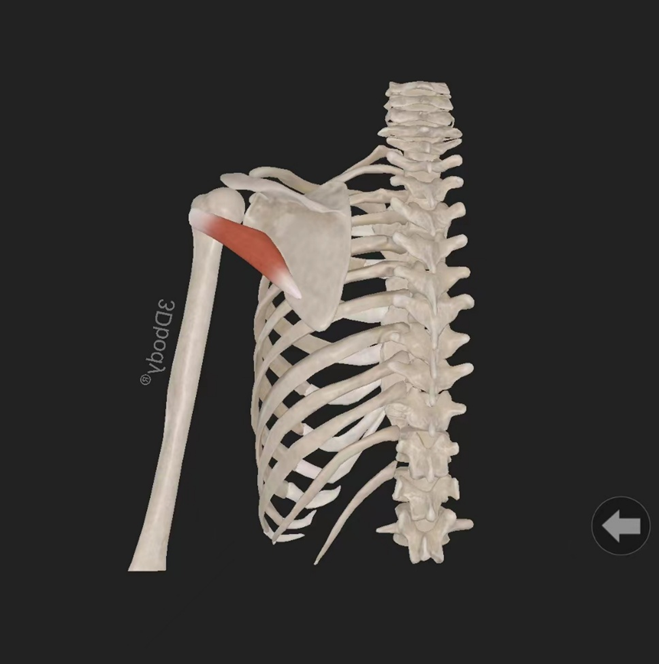

小圆肌:起自肩胛骨外侧缘背面,止于肱骨大结节下部。由腋神经(C5—7)支配。作用:使关节旋外。

冈上肌:起自冈上窝,穿过肩峰和喙肩韧带,止于肱骨大结节上部部。由肩胛上神经(C5—6)支配。作用:使肩关节外展。

冈下肌:起自冈下窝内,止于肱骨大结节中部。由腋神经(C5—7)支配。作用:使关节旋外。

肩胛下肌:起自肩胛下窝(肩胛骨前面),止于肱骨小结节。由肩胛下神经(C5—6)支配。作用:使肩关节旋内、内收。